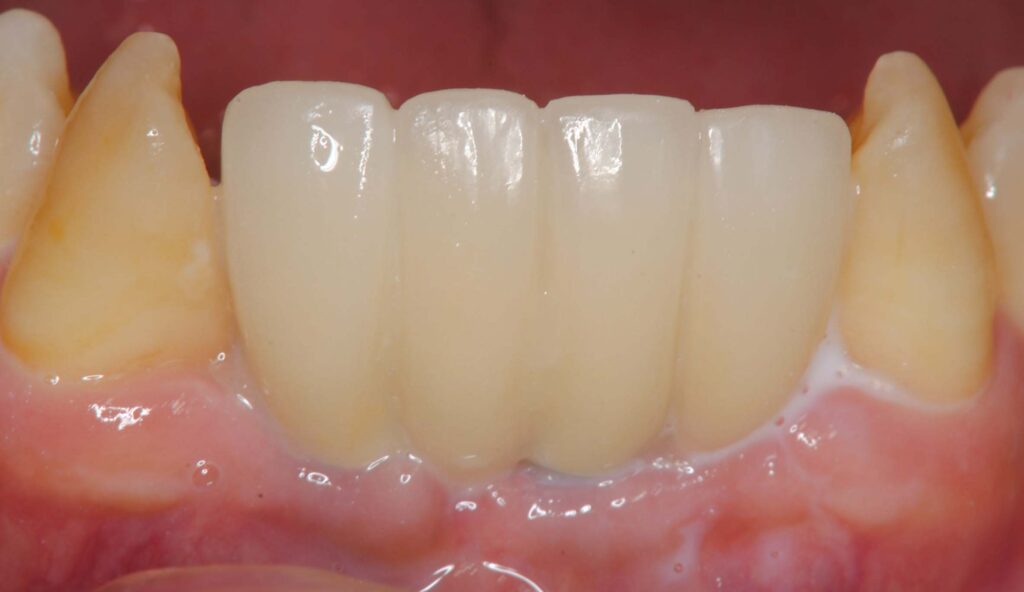

下顎前歯部インプラント 2026 3/09 臨床アラカルト 2026年2月17日2026年3月9日 歯周病で下顎の前歯を4本失った方です。最終的にこんな形で修復しました。 臨床アラカルト よかったらシェアしてね! URLをコピーしました! URLをコピーしました! 矯正実習セミナーに参加してきました。 博多歯周外科実習セミナー 関連記事 学んだばかりの技術を活かす(歯周組織再生療法) 2026年5月11日 患者さんから学ぶ 2026年4月20日 80歳の方の矯正 2026年3月24日 学んだ事を早速応用しました 2026年3月10日 トラブルシューティング 2026年2月4日 80歳で矯正を希望された方 2025年12月26日 貼物作り 2025年11月27日 歯科は考古学? 2025年11月6日 コメント コメントする コメントをキャンセルコメント ※ 名前 ※ メール ※ サイト 次回のコメントで使用するためブラウザーに自分の名前、メールアドレス、サイトを保存する。 上に表示された文字を入力してください。